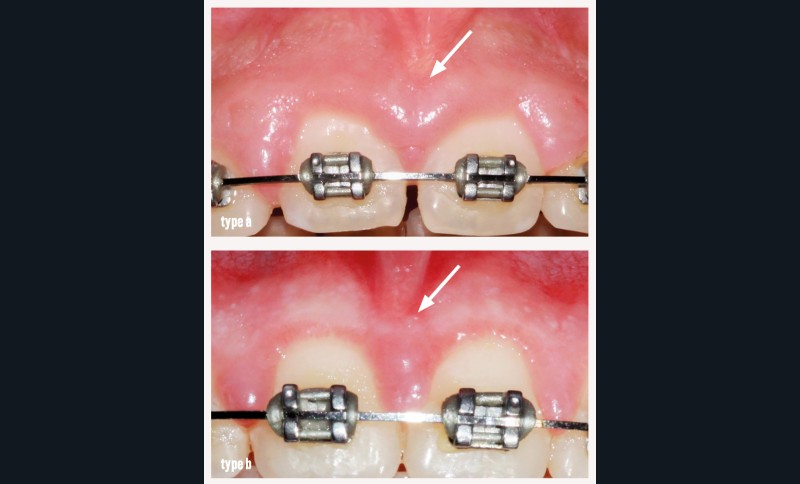

• type b : frein avec une insertion au niveau de la gencive attachée ;

L’examen clinique met en évidence au niveau du secteur incisif maxillaire (fig. 1a, b) :

- la persistance du diastème interincisif ;

- un frein labial médian, érythémateux, avec une insertion coronaire hypertrophique, algique à la palpation et à la traction de la lèvre, qui mobilise par ailleurs la gencive libre mésiale des incisives centrales et la papille ;